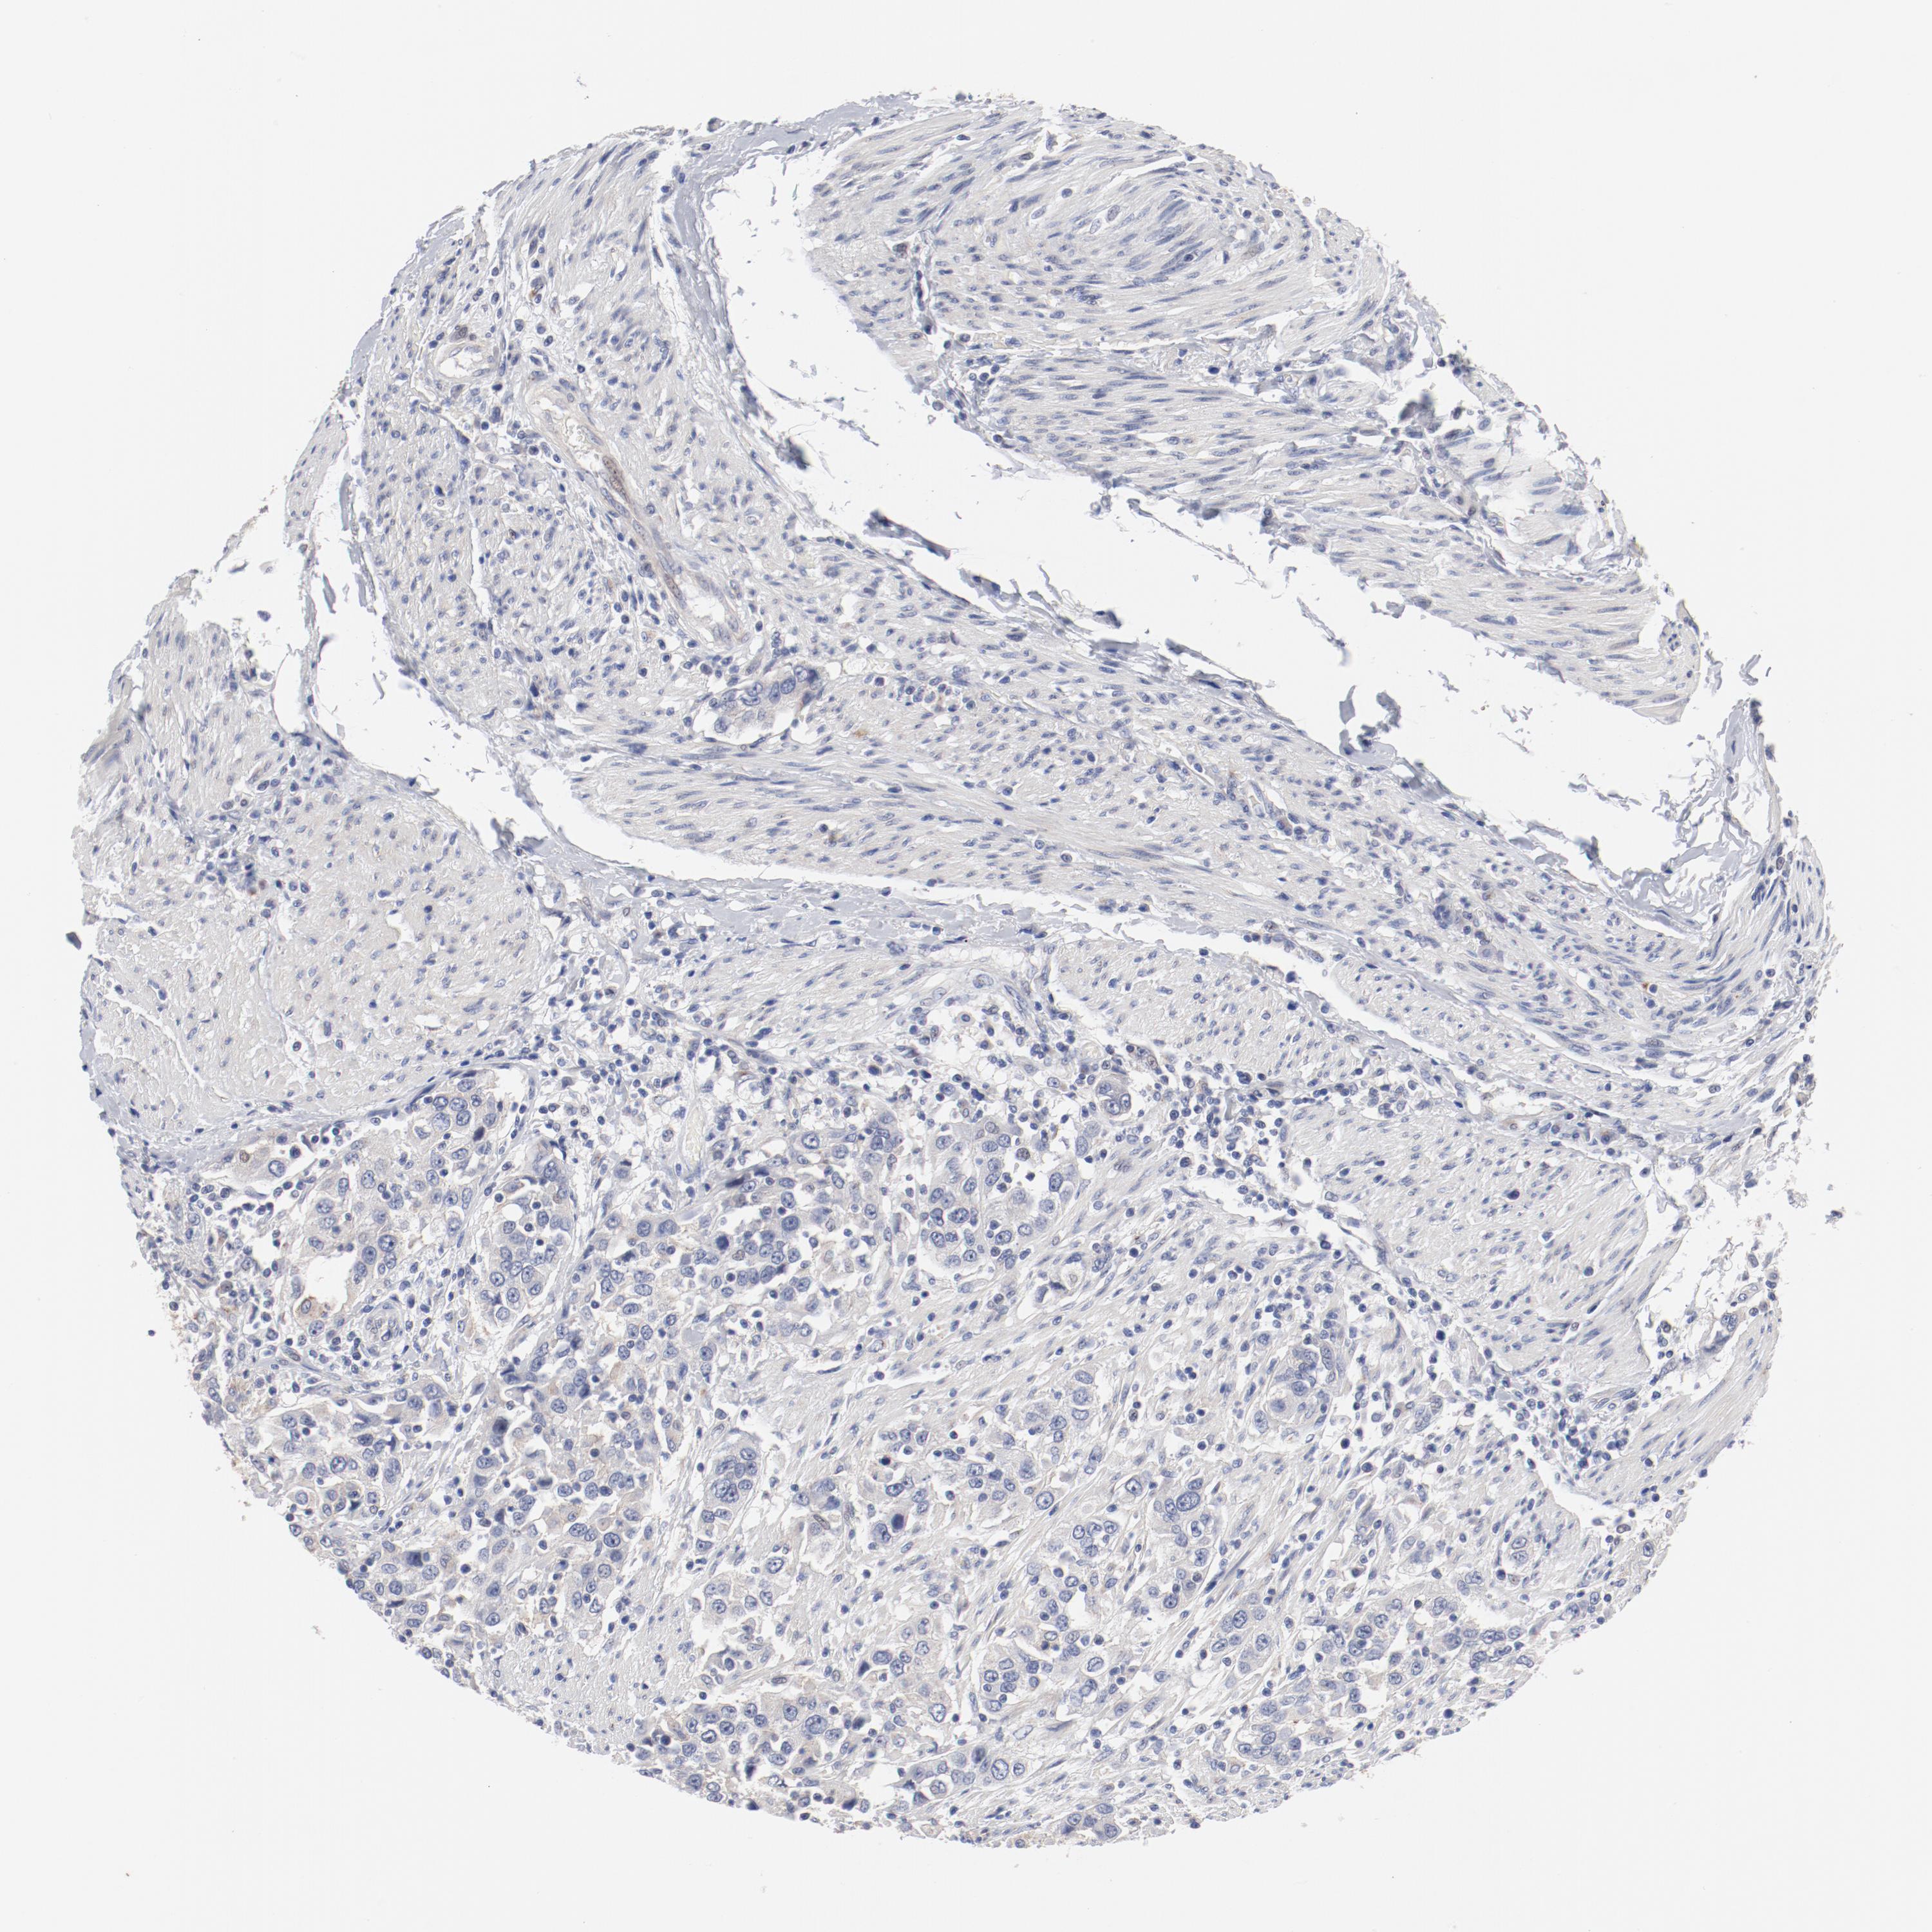

UROTHELIAL CANCER - Protein expressioni

A mouse-over function shows sample information and annotation data. Click on an image to view it in a full screen mode. Samples can be filtered based on level of antibody staining by selecting one or several of the following categories: high, medium, low and not detected. The assay and annotation is described here.

Note that samples used for immunohistochemistry by the Human Protein Atlas do not correspond to samples in the TCGA dataset.

Antibody stainingi

Antibody staining in the annotated cell types in the current human tissue is reported as not detected, low, medium, or high, based on conventional immunohistochemistry profiling in selected tissues. This score is based on the combination of the staining intensity and fraction of stained cells.

Each image is clickable and will lead to virtual microscopy that enables deeper exploration of all samples and also displays staining intensity scores, fraction scores and subcellular localization as well as patient and tissue information for each sample.

Antibody HPA003648

Staining

High

Medium

Low

Not detected

Intensity

Strong

Moderate

Weak

Negative

Quantity

>75%

75%-25%

<25%

None

Location

Nuclear

Cytoplasmic/membranous

Cytoplasmic/membranous,nuclear

Urothelial carcinoma, High grade

Urothelial carcinoma, Low grade